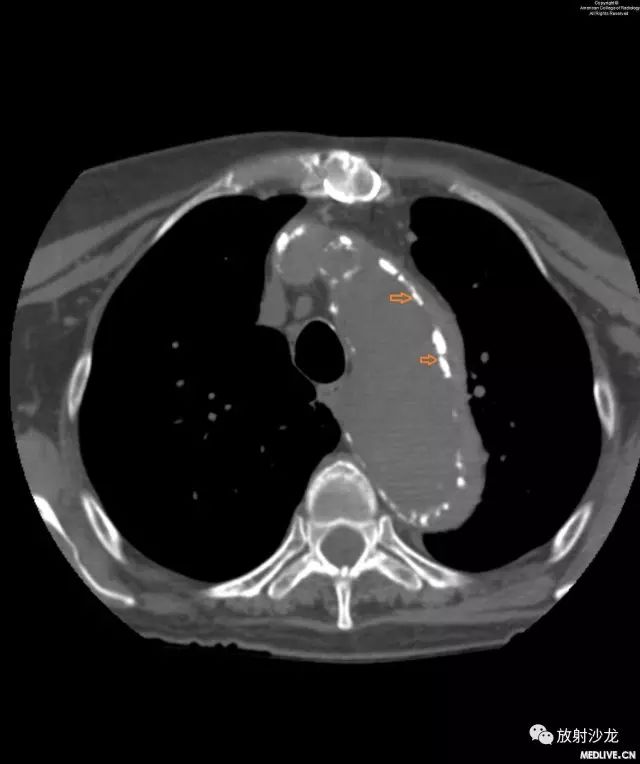

图3和图4:CT平扫和增强扫描显示由于壁内血肿(intramural hematoma,IMH)而移位的主动脉钙化。注意IMH呈稍高密度影,这提示出血是急性的。